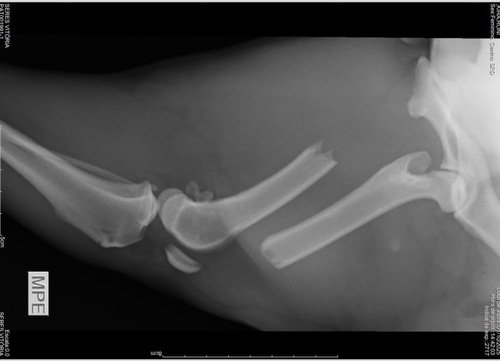

No dia 29/09/2025, nossa Cadela de nome Kina, Fugiu de casa e voltou no dia Seguinte machuca pelo jeito, ela foi atingida por algum veículo enquanto Corria algo que ela ama fazer. O resultado foi uma fratura no fêmur, confirmada no raio-X.